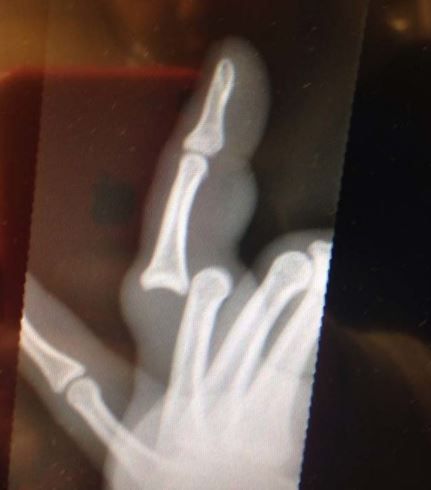

/ 8Palec wskazujący

A mama mówiła: "Nie pokazuj palcem". Teraz już wie dlaczego.